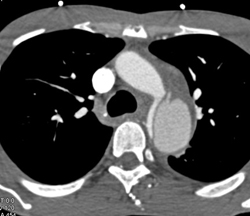

Aberrant Right Subclavian Artery With Aneurysm